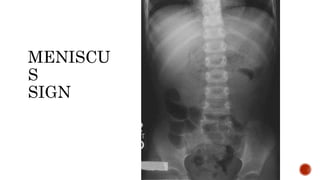

 Meniscus sign:

 Crescent of gas within colonic lumen that outlines the apex of intussusceptum.

 Little air in small intestine.

MENISCU

S

SIGN